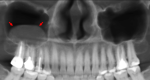

: QUISTE DENTIGERO